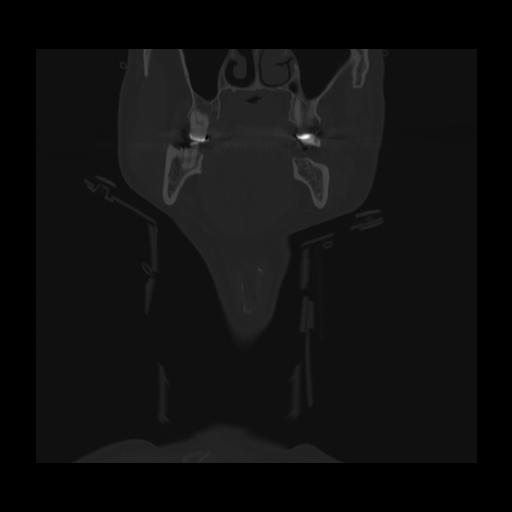

16 HUESO,,Coronal,2.000,HUESO,Coronal,